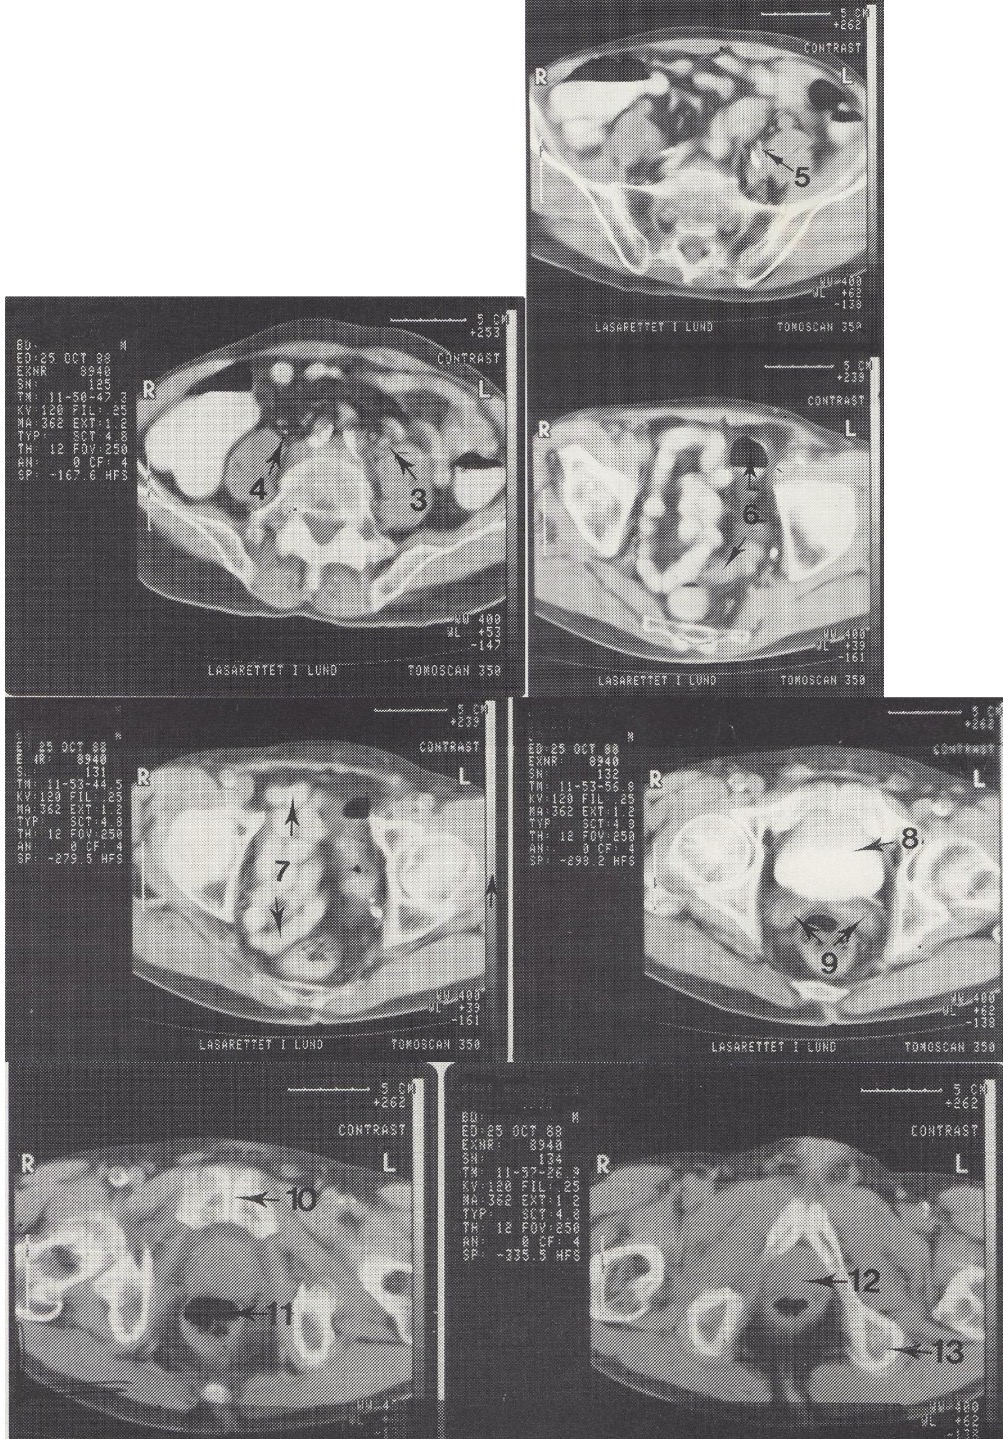

1

Aorta abdominalis (kalcifikuota pilvinė aorta)

2

M. psoas major (didysis juosmens raumuo)

3

Ureter sinister (kairysis šlapimtakis, šiek tiek praplėstas)

4

Ureter dexter (dešinysis šlapimtakis)

Metodika

KT pjūviai nuo juosmens slankstelių iki gaktinės sąvaržos apačios. Suleistas intraveninis kontrastas (išryškina šlapimo takus) ir išgertas kontrastas (išryškina žarnyną).

Radiniai

Gausūs apkalkėjimai (kalcifikatai) aplink pilvinę aortą ir vidines klubo arterijas. Kairysis šlapimtakis matomas priešais m. psoas major, jis šiek tiek išsiplėtęs.